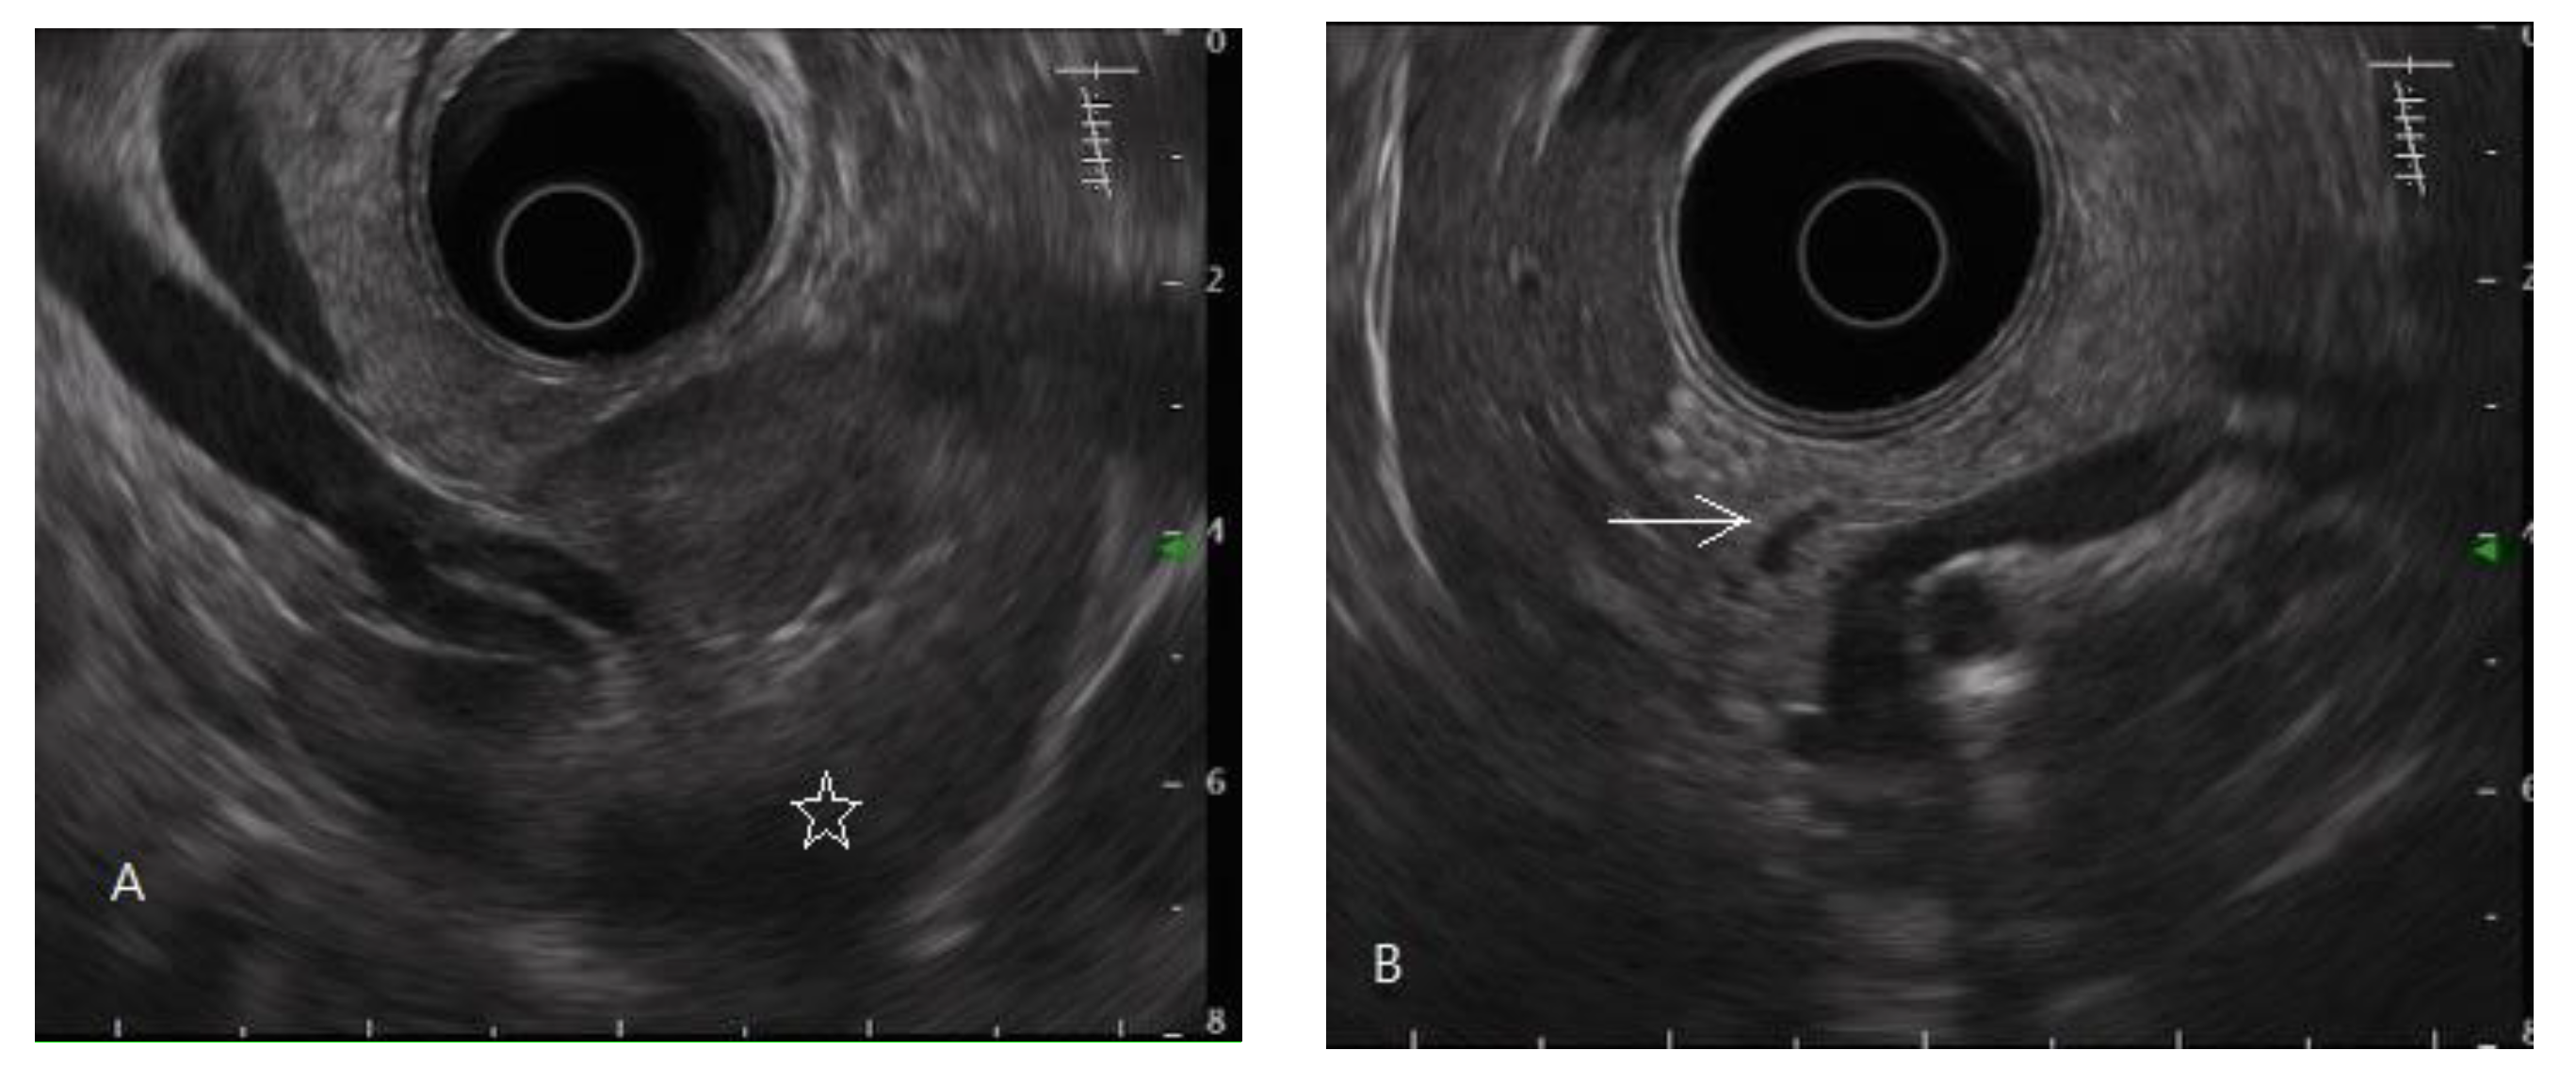

- Domínguez-Muñoz, J.E.; Lariño-Noia, J.; Alvarez-Castro, A.; Nieto, L.; Lojo, S.; Leal, S.; Iglesia-Garcia, D.; Iglesias-Garcia, J. Endoscopic ultrasound-based multimodal evaluation of the pancreas in patients with suspected early chronic pancreatitis. United Eur. Gastroenterol. J. 2020, 8, 790–797. [Google Scholar] [CrossRef]